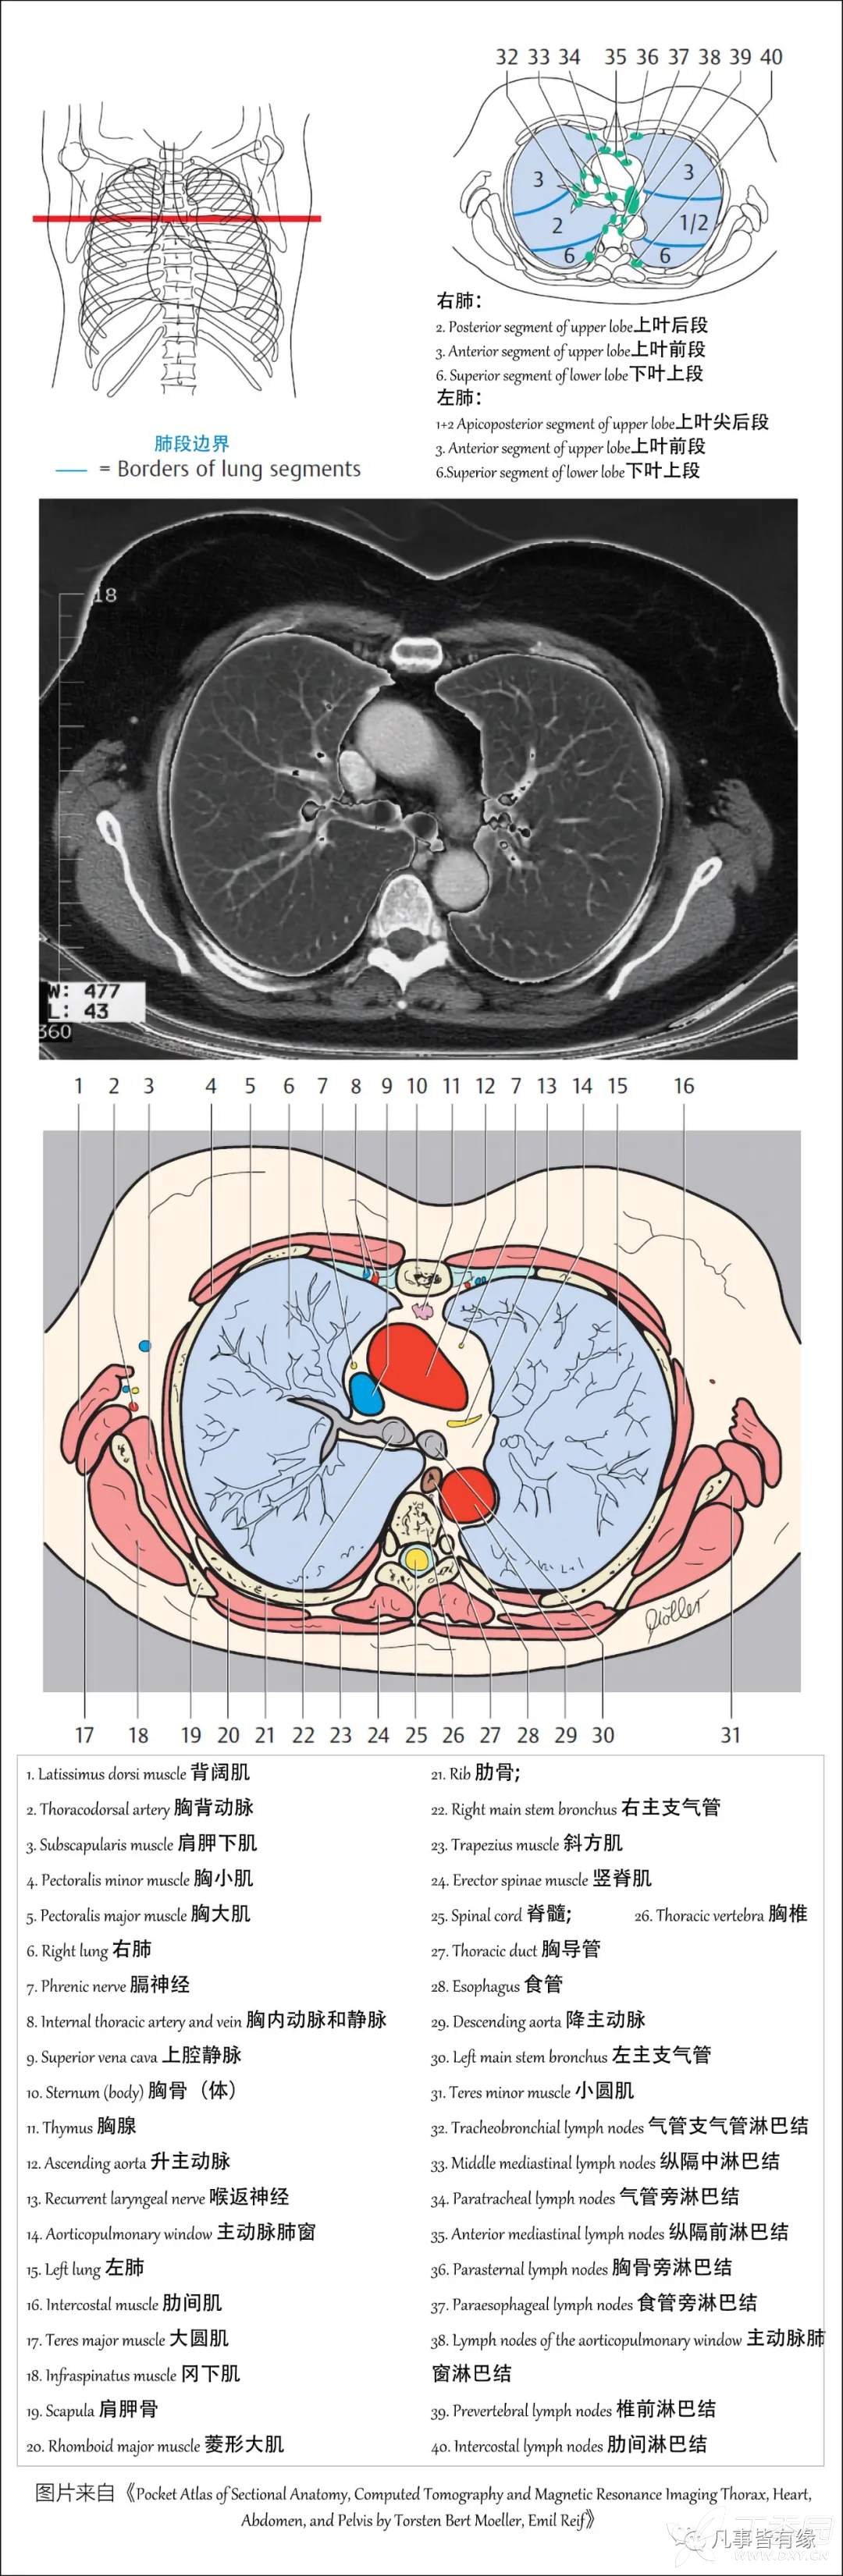

(一)胸部CT轴位断层解剖:

右肺(RightLung)

2.Posterior segment of upper lobe 上叶后段

3.Anterior segment of upper lobe 上叶前段

6.Superior segment of lower lobe 下叶上段

左肺(LeftLung)

1+2Apicoposterior segment of upper lobe 上叶尖后段